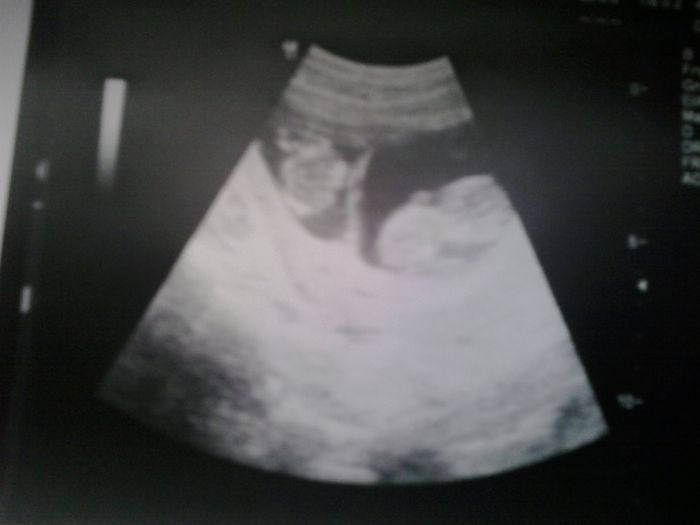

Jeste pridavam fotku te nasi pidalky. Konecne je poradne videt :-)

Tedaa, to je povedená fotecka, nádhera ! :)

Pomenko 10cm to je nadhera. My meli ve 12+5 6,5cm. Pan doktor rikal,ze je vse o.k.i velikost. Tak snad ano.

Holky dekuju :-) Sari krasna fotecka dvojcatek :-) tak at nam ty deti krasne rostou a vsem se nam dari. Tesim se na dalsi fotecky a dobre zpravy :-)